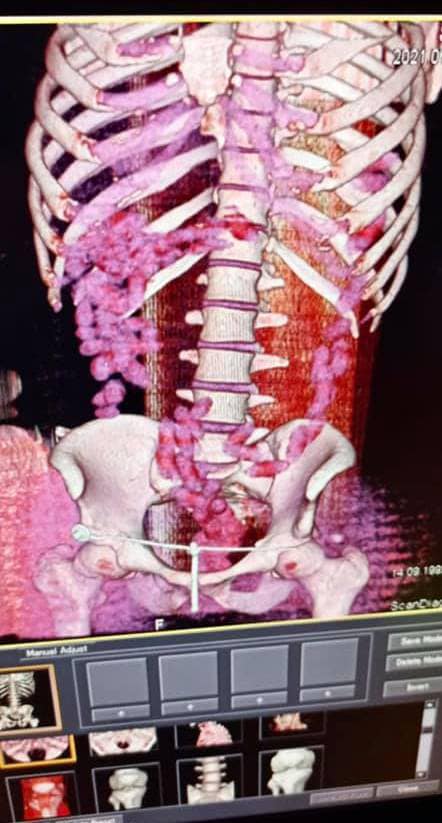

"В июле 2021 года в Борисполе был задержан бразилец, который в желудке ввез в Украину почти 1 кг кокаина. Мужчина проглотил 90 капсул, которые извлекали из кишечника медикаментозным путем после компьютерной томографии", - говорится в сообщении.

Напомним, 29-летний курьер с начиненными кокаином капсулами в желудке прибыл в аэропорт "Борисполь". Имея предварительную оперативную информацию, таможенники применили в отношении иностранца личный досмотр с привлечением медицинского работника. Процедура проходила в медицинском учреждении с применением компьютерной томографии брюшной полости мужчины.

Изъятие 90 капсул овальной формы, которые находились в его кишечнике, происходило медикаментозным путем и длилось почти три часа.